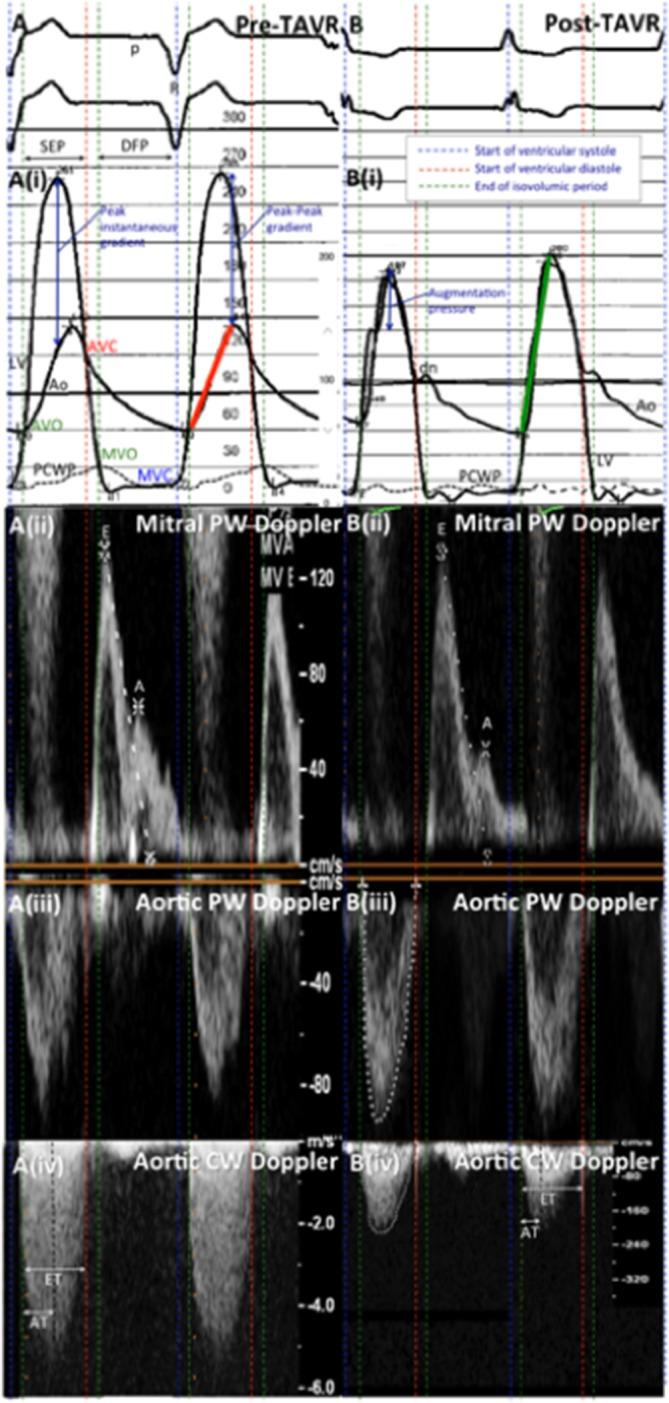

Transcatheter aortic valve replacement (TAVR) has become the preferred therapy for treatment of severe aortic stenosis in patients at intermediate to high risk of perioperative mortality following surgical aortic valve replacement. Haemodynamic assessment is an integral part of the procedure, and it is crucial for the operator to have an in-depth understanding of the haemodynamic alterations that occur during balloon aortic valvuloplasty and transcatheter valve deployment. Comprehension of the haemodynamic tracings is also pivotal for early recognition of periprocedural complications. With expanding indications for TAVR, it is imperative for members of the structural heart team to have an in-depth, nuanced understanding of transcatheter haemodynamic waveforms and their correlation with echocardiographic Doppler waveforms that are obtained periprocedurally during TAVR. This review provides a collection of transcatheter haemodynamic tracings and their corresponding Doppler echocardiography correlates that are demonstrative of physiological alterations and pathological lesions (complications) that occur during TAVR.